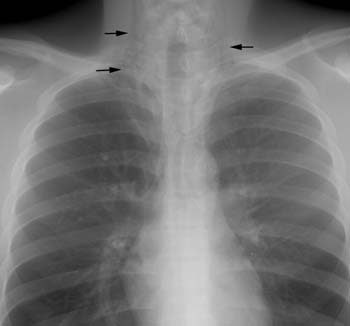

Pneumomediastinum:

The patient shown below presented with chest pain after swimming. Vertically oriented radiolucencies can be seen in the lower neck bilaterally. Vertical lucencies can also be seen anterior to the heart and great vessels within the anterior mediastinum on the lateral view.